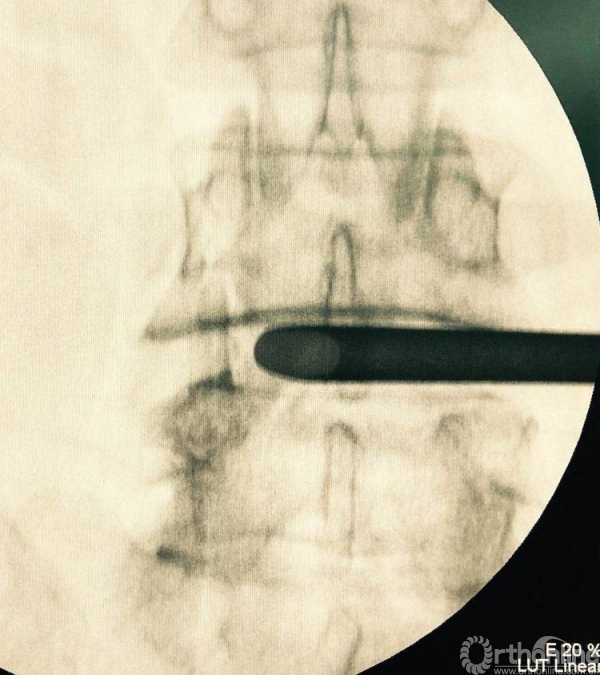

植入椎板钉、开路椎、扩展管、克氏针以及动力钻等应用

植入经皮椎弓根钉并加压

术后正、侧位片

植入钉棒位置较为合理

矢状位融合器、植骨位置及滑脱复位情况